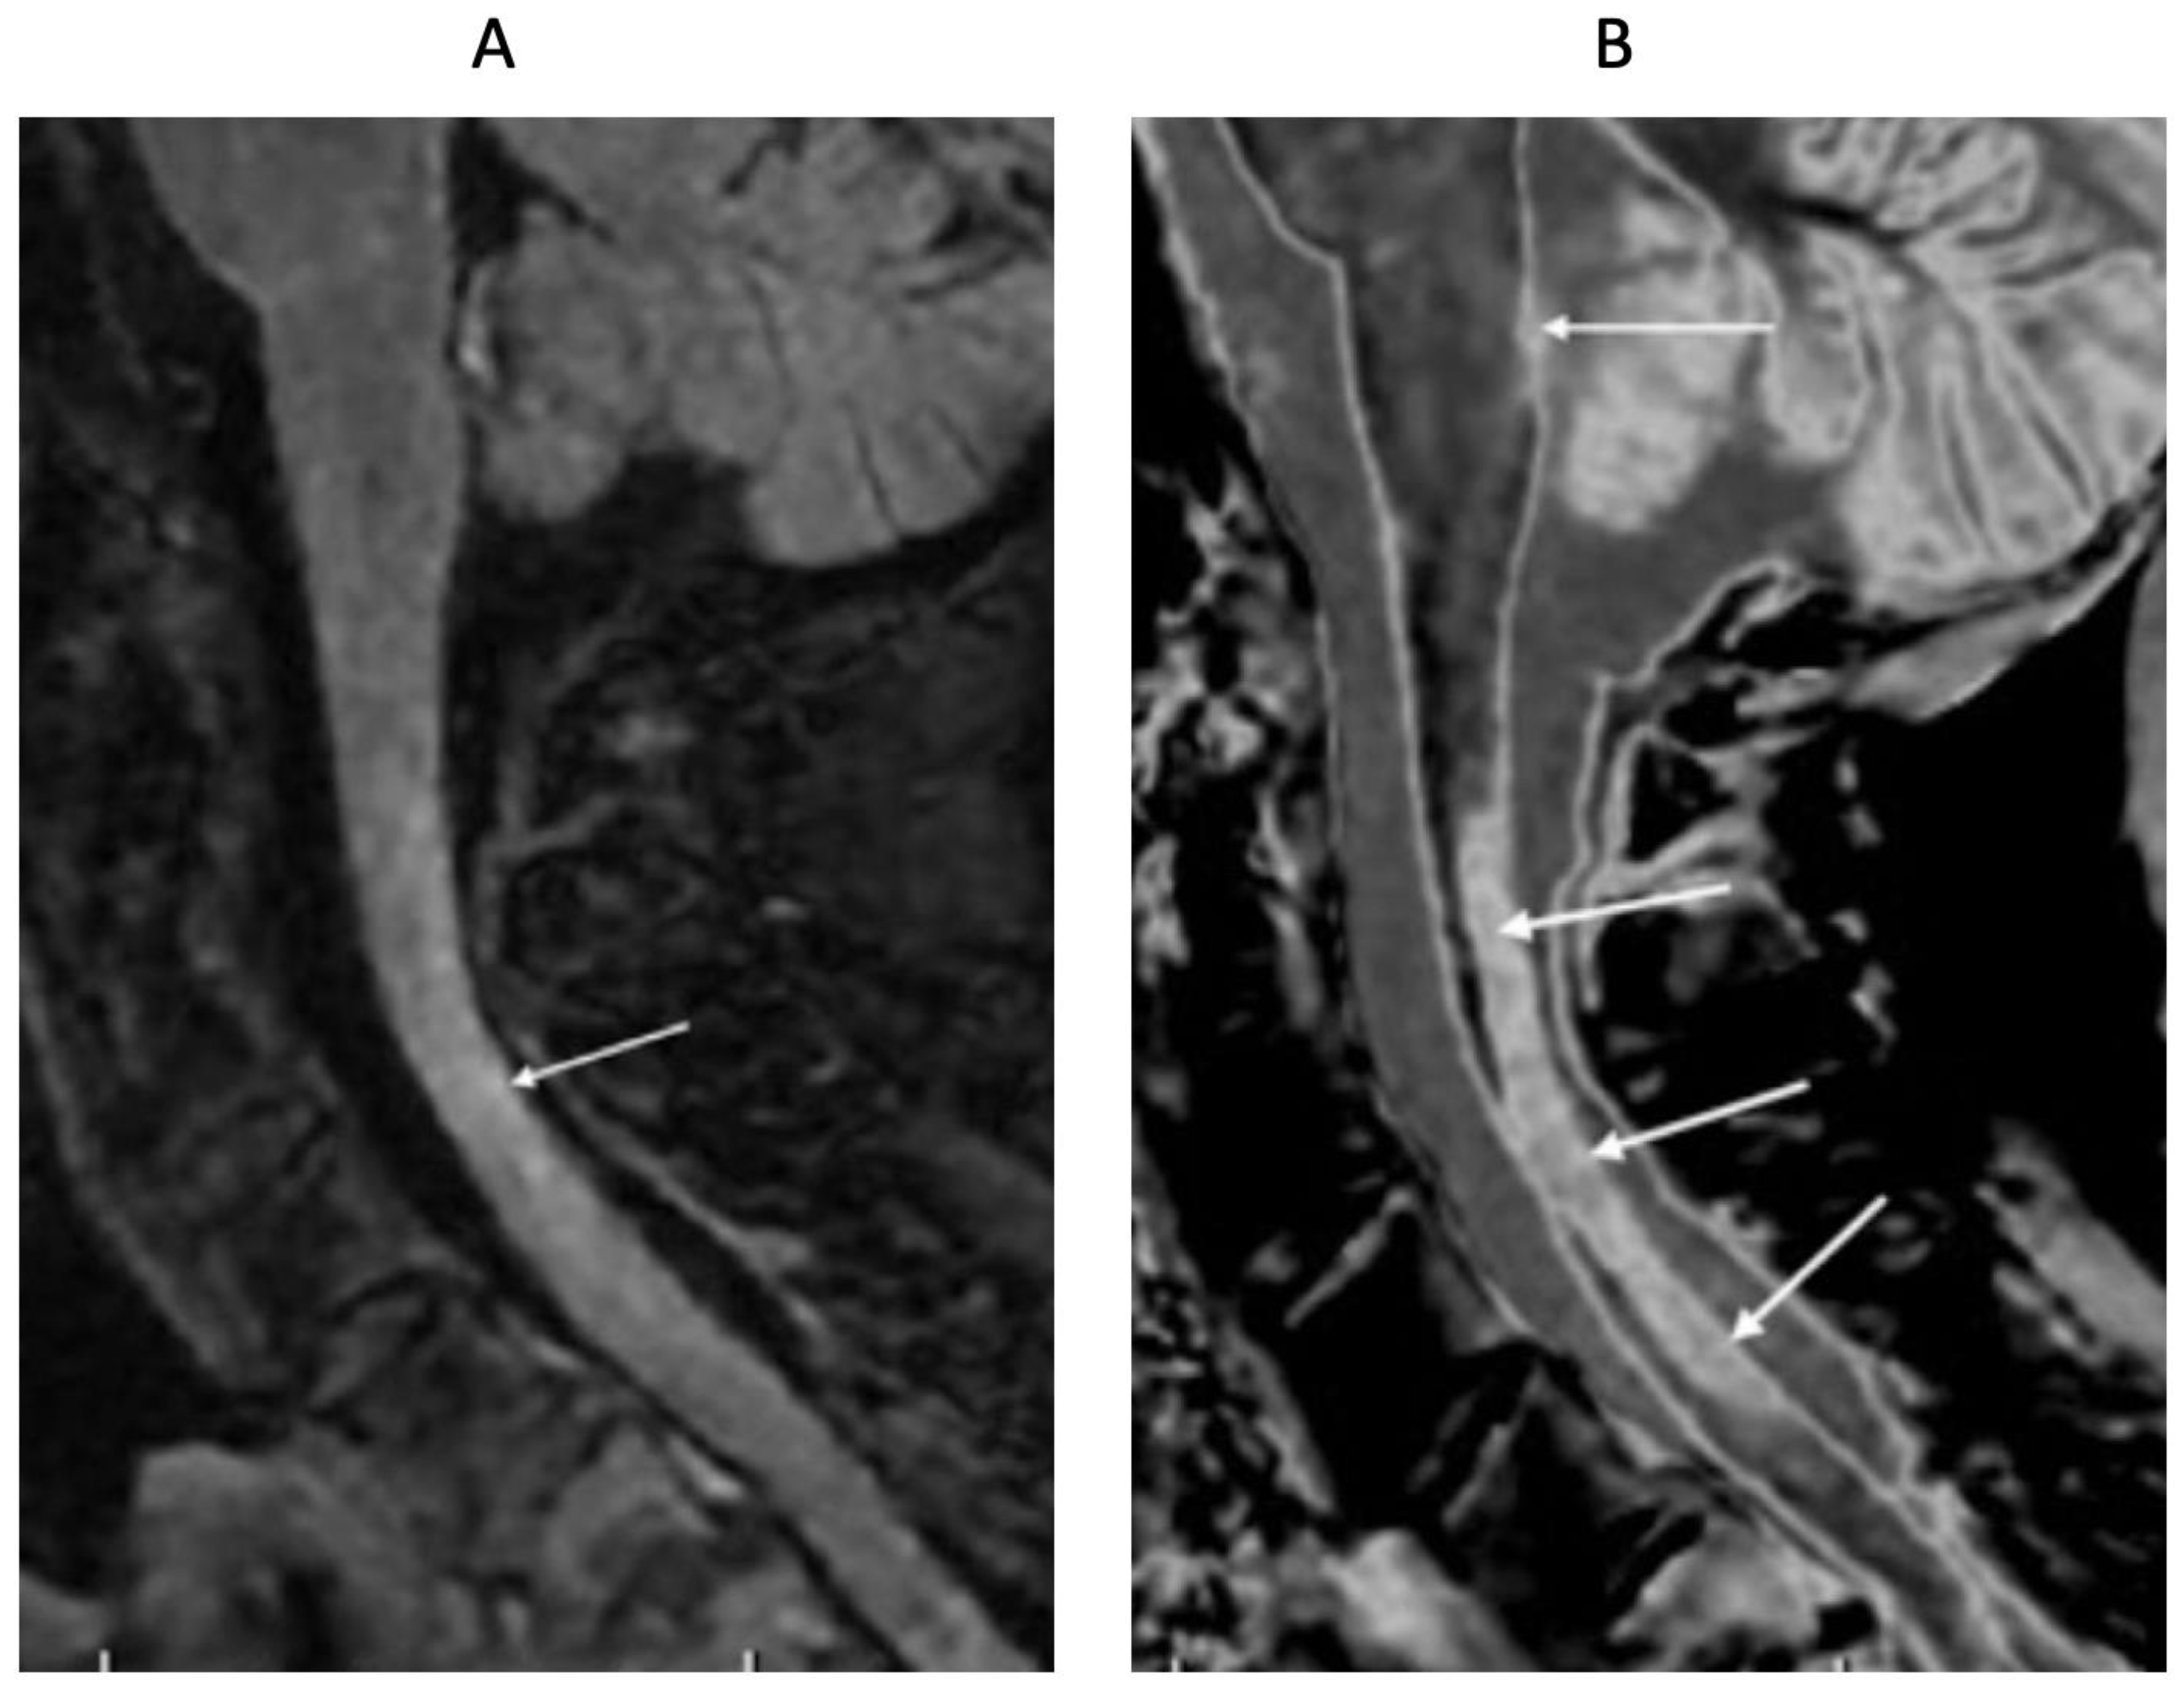

4. Illustrative Cases

5.2. Signs

5.3. Clinical Issues